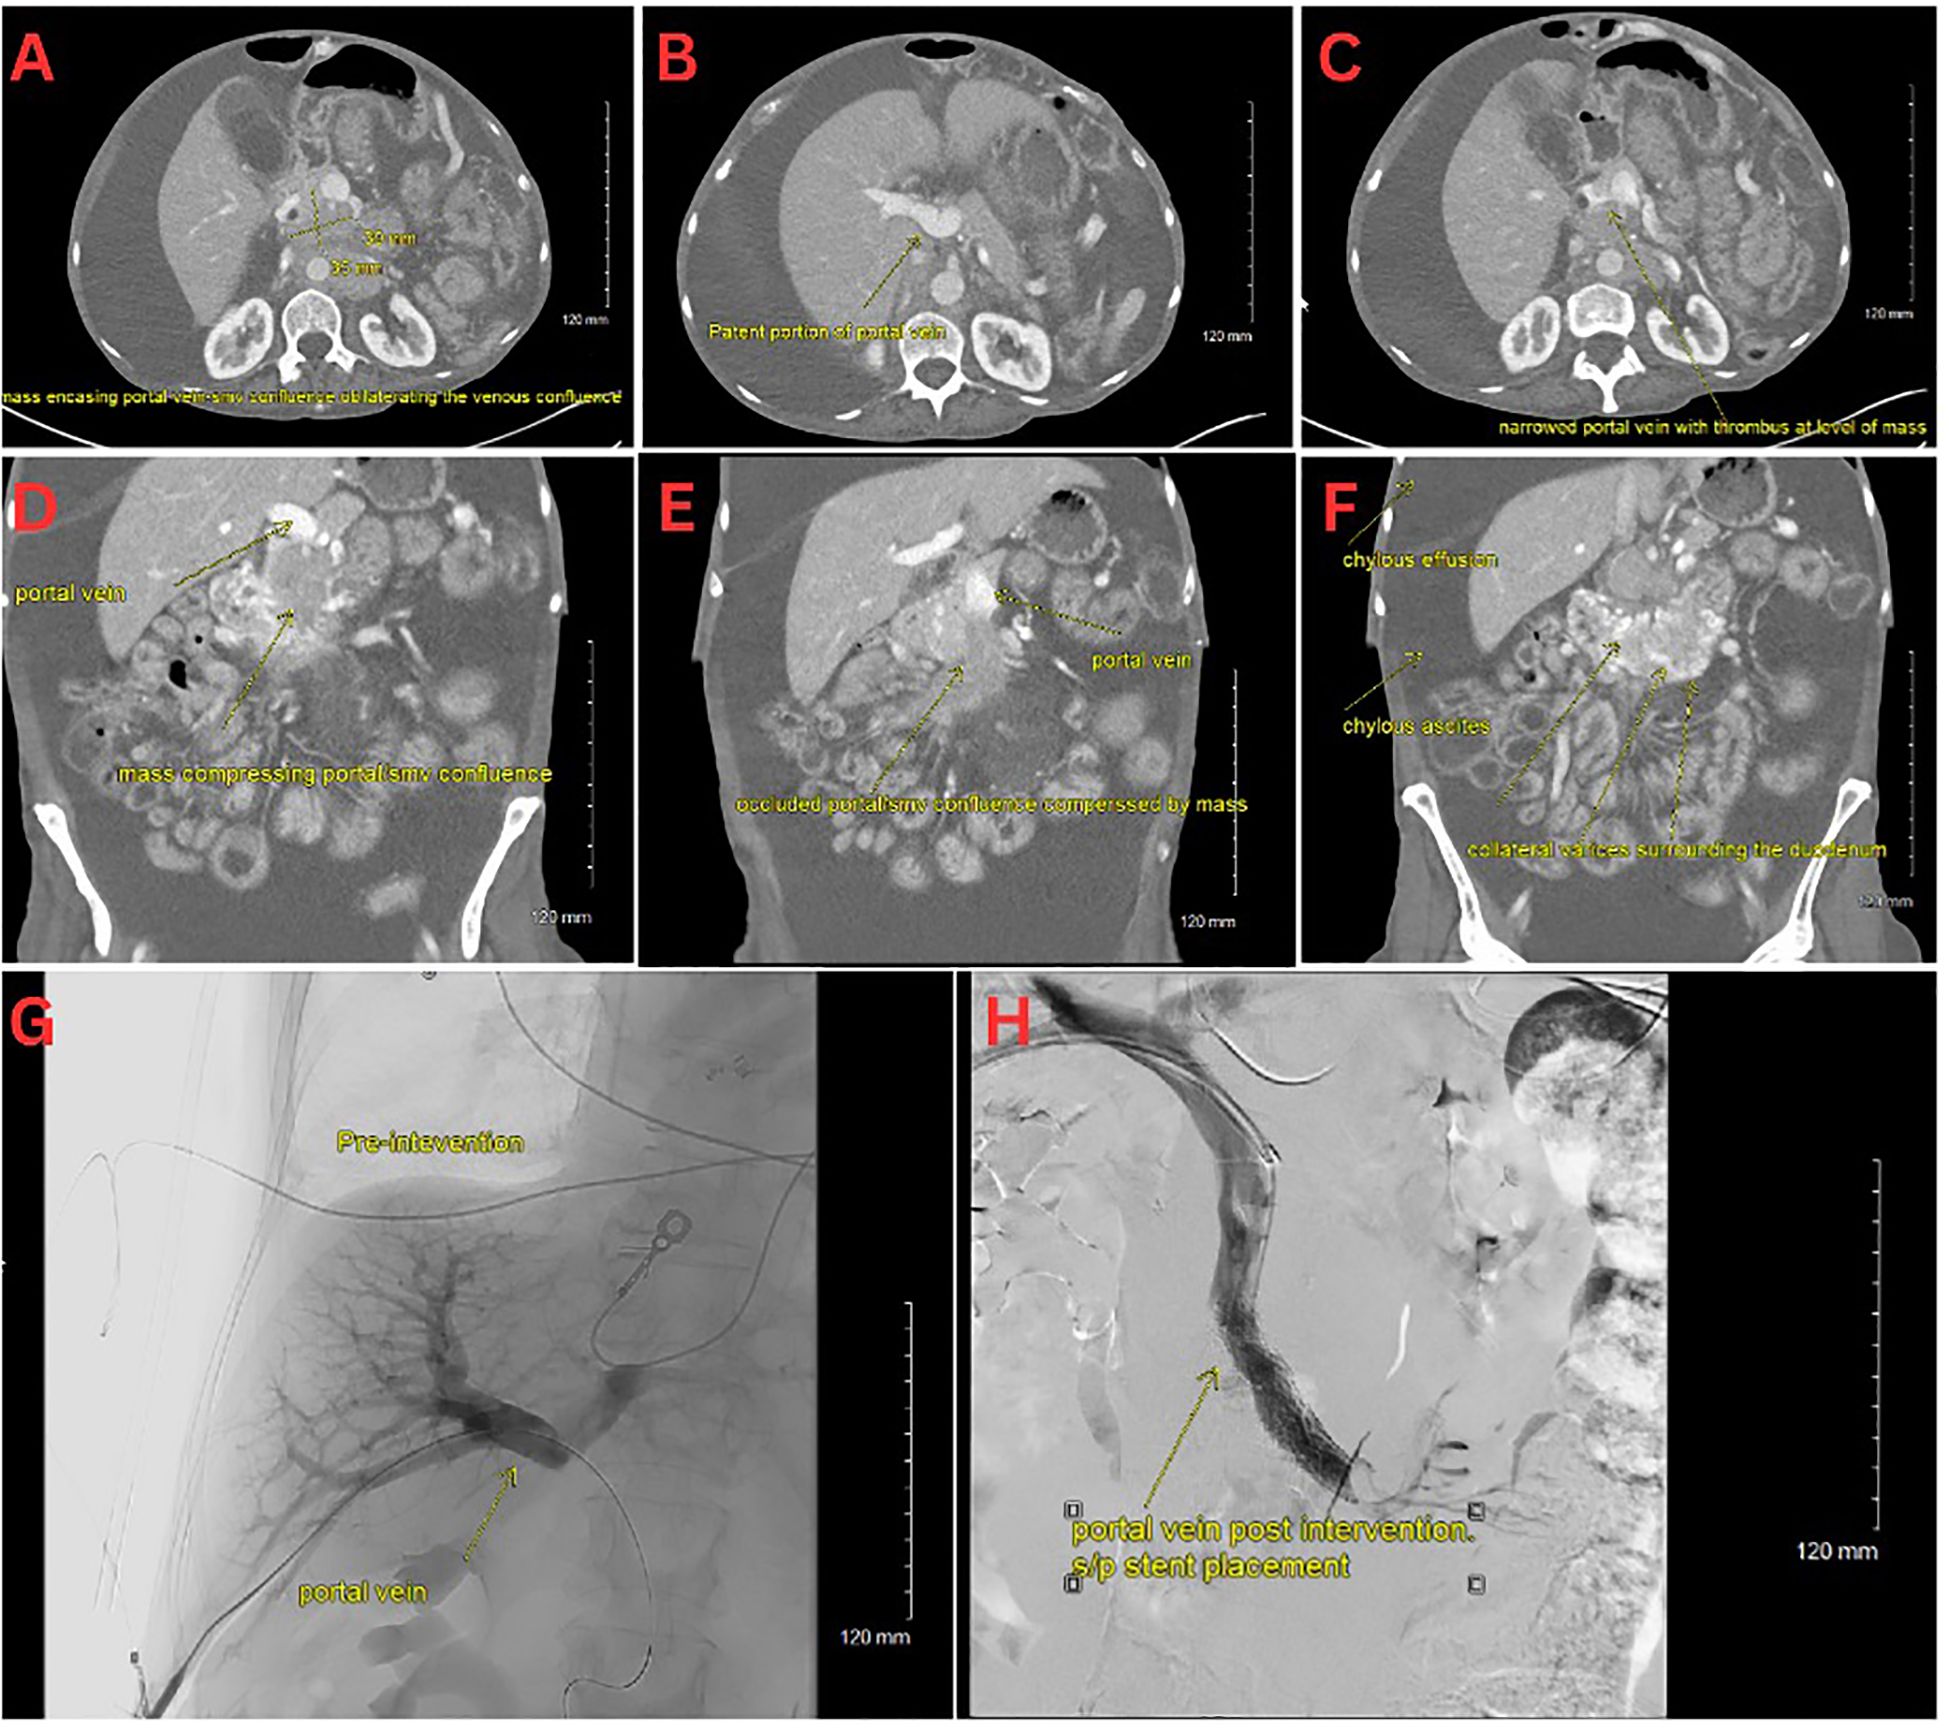

On initial evaluation, she appeared cachectic, tachycardic (110 bpm), tachypneic, and had an oxygen saturation of 87% on room air. She had conjunctival pallor, severely diminished breath sounds on the right side, massive abdominal distension with diffuse dullness to percussion, and bilateral pitting edema extending to the thighs. Notable laboratory results included mild thrombocytosis (platelets 471 x 10^3/µL), hypokalemia (K 2.7 mmol/L), hypoalbuminemia (3.2 g/dL), and hypomagnesemia (0.9 mg/dL), and an elevated troponin levels (28, 27, 24 ng/L). A chest CT showed a massive right pleural effusion with leftward cardio-mediastinal shift and near-complete right lung collapse. Additionally, segmental pulmonary emboli were found in the left lower lobe (Figures 1A–F). Abdominal CT revealed a heterogeneous pancreatic head/uncinate mass with encasement of the superior mesenteric artery (SMA) and mass effect on the SMV, retroperitoneal lymphadenopathy, and sclerotic bone lesions.

Interventional radiology performed a transhepatic portal venogram, demonstrating a 20 cm H2O gradient across the SMV obstruction, along with extensive varices. A 12 mm x 60 mm self-expanding stent was deployed, reducing the gradient from 20 to 10 cm H2O and restoring antegrade hepatopetal flow (Figures 1G–H). Post-procedure, her abdominal distension, and chylothorax gradually improved, and large-volume paracenteses were no longer required. She was started on total parenteral nutrition (TPN) and long-acting octreotide for symptom management.

A series of medical images labeled A to H show various CT scans and radiographs of the abdominal area focusing on the portal vein and related structures. Images A-F display different sections and planes where the mass and its effects on adjacent vessels are shown, including compression and narrowing of the portal vein. Image G presents a pre-intervention radiograph, highlighting the portal vein. Image H shows a post-intervention radiograph, indicating changes after stent placement. Annotations identify specific features like thrombus, chylous ascites, and collateral vessels.

Figure 1. (A–C) CT scan with an axial view of the pNET mass. (D–F) CT scan with a coronal view of the pNET mass. (G) Venogram showing portal vein prior to stent deployment with no distal contrast visualized. (H) Venogram post SMV stent deployment with subsequent patency.